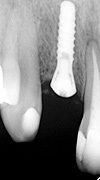

症例 13

① 前歯1本がないところにインプラントを埋め込んだレントゲン写真です。

② 最終的な歯が入りメンテナンス中のレントゲン写真です。

30才代 女性

総額:42万円(税別)

治療期間:4ヵ月

リスク副作用:経年的に骨が吸収すると審美障害が生ずることがあります。